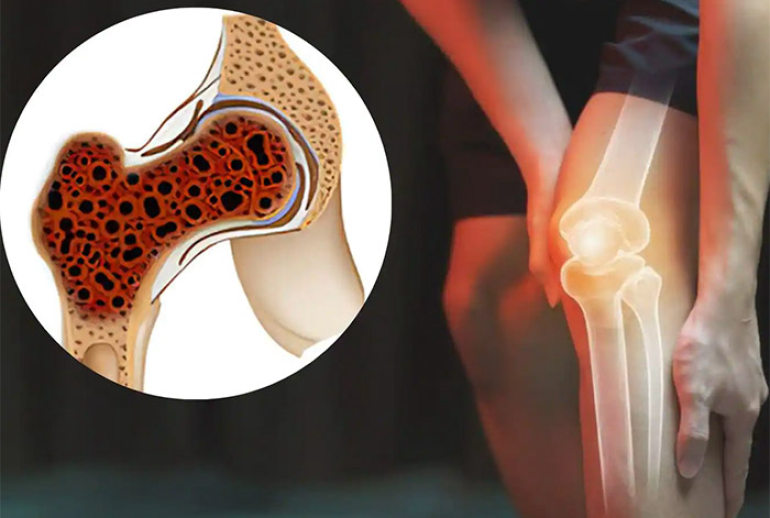

سارکوم یوئینگ (Ewing Sarcoma) یکی از انواع نادر سرطان است که بهطور عمده در استخوانها یا بافتهای نرم اطراف آن ایجاد میشود. این سرطان بیشتر در کودکان و نوجوانان بروز میکند، اما افراد بزرگسال نیز ممکن است به آن مبتلا شوند. نام این سرطان از دکتر جیمز یوئینگ گرفته شده که برای اولین بار این بیماری را در اوایل قرن بیستم توصیف کرد. سارکوم یوئینگ یک نوع از سرطانهای تهاجمی است که میتواند به سرعت گسترش یابد و به دیگر نواحی بدن سرایت کند. از این رو، تشخیص و درمان به موقع این بیماری بسیار حیاتی است.

علت دقیق بروز سارکوم یوئینگ هنوز بهطور کامل مشخص نیست، اما تحقیقات نشان داده که این سرطان با برخی تغییرات ژنتیکی در سلولهای بدن ارتباط دارد. در اغلب موارد، تغییرات کروموزومی و جابجایی ژنها در سلولهای بدن ممکن است باعث ایجاد این نوع سرطان شوند. این جابجاییها به ایجاد پروتئینهای غیرطبیعی در سلولها منجر میشوند که باعث رشد و تقسیم کنترل نشده سلولها و تشکیل تومور میشود.

یکی از مهمترین علائم سارکوم یوئینگ، درد مداوم و شدید در ناحیه استخوانهای درگیر است. این درد معمولاً با گذشت زمان شدیدتر میشود و ممکن است به دیگر نواحی بدن سرایت کند.

در برخی موارد، بیمار ممکن است یک توده یا تورم در ناحیه مبتلا به سرطان مشاهده کند. این تورم ممکن است همراه با درد باشد یا بدون درد باشد.